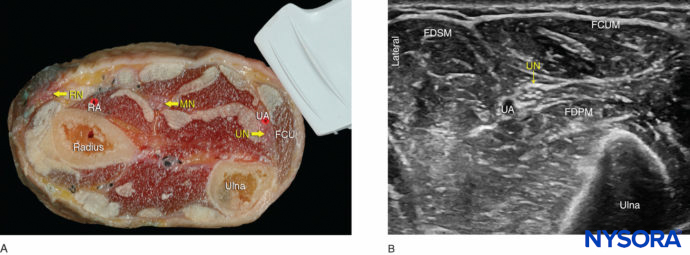

FIGURE 4. (A) Cross-sectional anatomy of the distal forearm. (B) Sonoanatomy of the ulnar nerve (UN) at the forearm. UA, ulnar artery; FCUM, Flexor carpi ulnaris. FDPM, flexor digitorum profundus muscle; FDSM, flexor digitorum superficialis muscle.

FIGURE 5. Sonoanatomy of the ulnar nerve (UN) at the wrist: needle path to reach the UN at the wrist and approximate spread of local anesthetic (blue-shaded area) to anesthetize the UN. UA, ulnar artery.